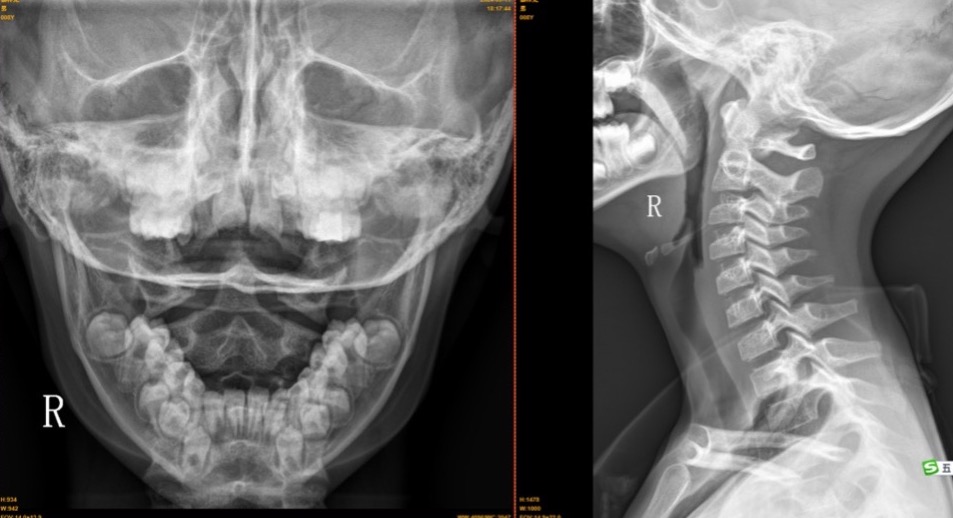

【影像】20240904龙华人民医院X线片报右环齿侧间隙变窄,环椎可疑前移位,不除外寰枢关节半脱位。C2椎体不稳,颈椎反弓伴向右侧凸。阅片见枢椎棘突偏右。

【诊断】寰枢关节半脱位

【结果】一次治疗颈椎基本正直,三次治疗后颈椎功能如常,复查X线片未见异常。